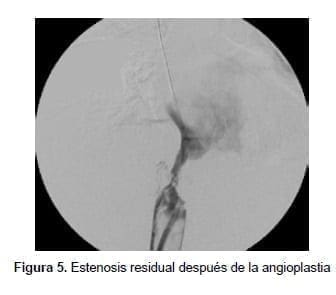

Procedió a realizar angioplastias secuenciales con balones de 10, 12 y 14 mm de diámetro (Boston Sci. Corp.), logrando repermeabilizar la vena cava, pero con una estenosis residual del 60 % (figura 5).